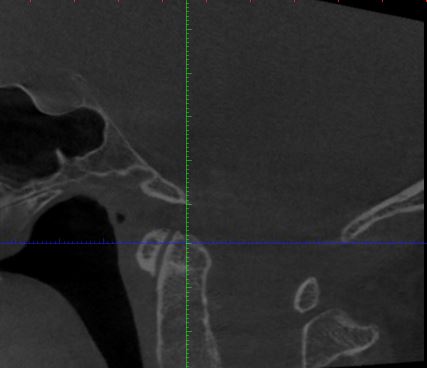

Der HNO Arzt vermutet die Halswirbelsäule als Ursache für den Tinnitus und hat eine DVT anfertigen lassen. Leider kann er die Aufnahmen nicht auswerten und sein Radiologe hat Urlaub. Kann von Euch jemand auf den angehängten Fotos etwas erkennen?